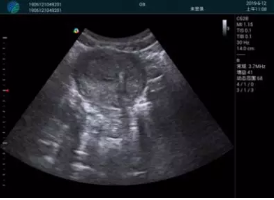

病例二:

腺體內(nèi)部清晰顯示一低回聲塊影,形態(tài)不規(guī)則,邊界模糊,邊緣呈毛刺狀,內(nèi)部見砂礫樣鈣化

M20引導(dǎo)下穿刺活檢術(shù)

M20引導(dǎo)下平面內(nèi)穿刺取出的腫塊組織